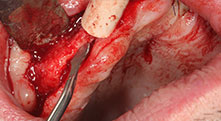

Could you describe briefly, for example, your procedure for mobilizing bone blocks for transplantation?

Bratu: We prefer to harvest bone from the external oblique ridge of the posterior mandible, not from the interforaminal region. After the soft-tissue incision, we use the new saws to define the amount of bone to harvest. With this approach, we also use them for the entire preparation in almost 80% of cases. We may also use other piezo instruments and then at the end a chisel to mobilize the block. We find that this is a very effective surgical technique.